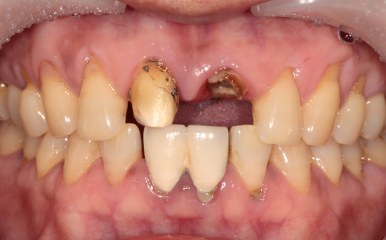

앞니 보철물이 빠져서 내원하시게 되신 환자분의 케이스입니다.

타원에서 치료받으신 보철물을 그동안 잘 사용하고 있었는데,

어제 갑자기 윗니 쪽으로 가벼운 충격이 있었고,

바로 보철물이 빠지셨다고 합니다.

2024. 1 기존의 보철물은 위 앞니 두 개를 연결한 형태였다고 하시네요.

환자분의 현재 상태를 보고 원인을 유추해 보았습니다.

기존에 연결된 앞니 보철물과 치아의 경계부 사이로 2차 충치가 진행이 오랜 기간 지속되었고,

보철물 내부의 치아에 충치가 심해져 약해져 있던 상태에서

작은 충격에 그 보철물이 빠져버리게 된 것입니다.